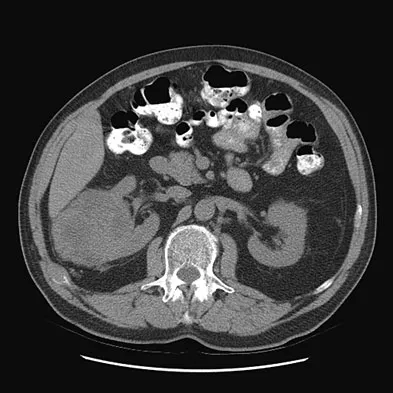

Figures 20a and 20b show the AP and lateral radiographs of a 62-year-old man who has had hip pain for the past 3 weeks. Figure 20c shows a CT scan of the abdomen and pelvis. A needle biopsy specimen is shown in Figure 20d. Preoperative management should include which of the following?

Explanation

The histology shows findings consistent with metastatic renal cell carcinoma. Renal cell carcinoma metastases are extremely vascular. Preoperative embolization helps minimize the amount of blood loss during curettage of these lesions. Chatziioannou AN, Johnson ME, Pneumaticos SG, et al: Preoperative embolization of bone metastases from renal cell carcinoma. Eur Radiol 2000;10:593-596.